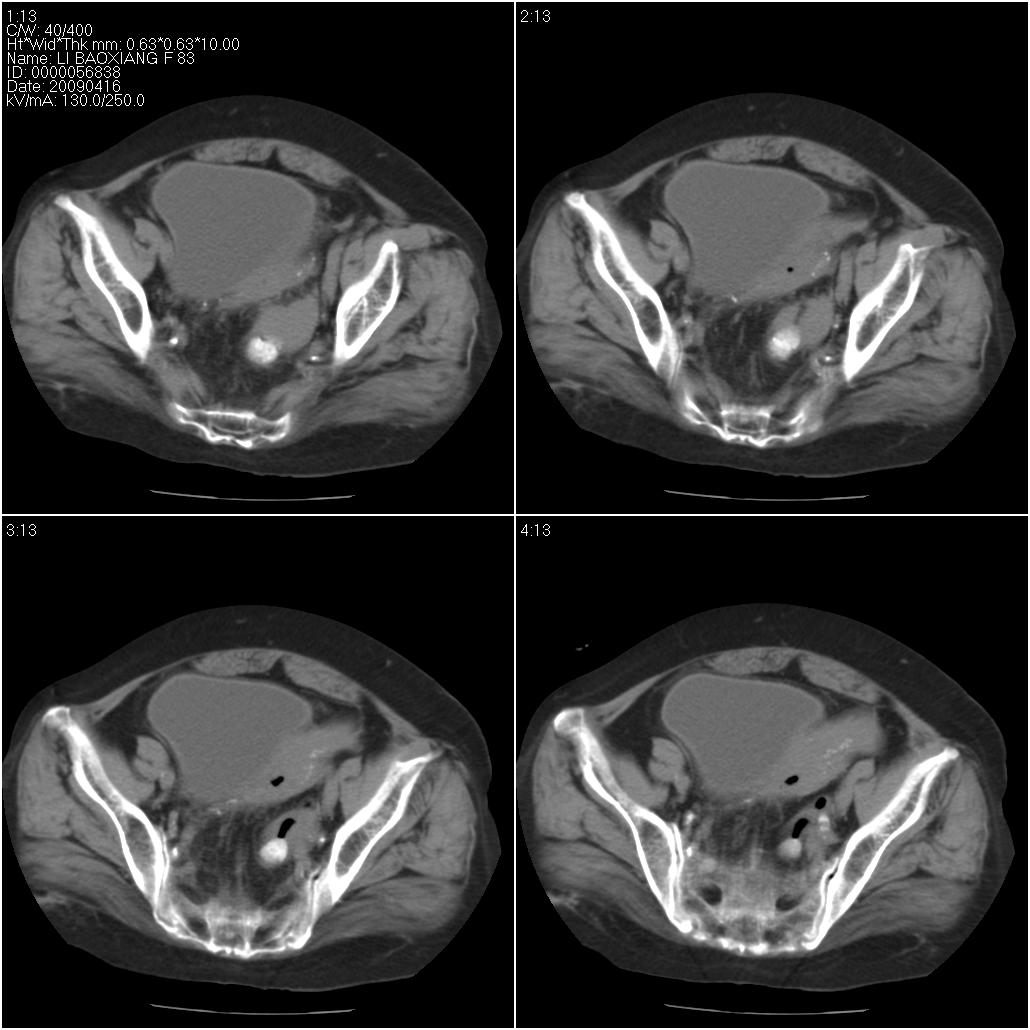

标题: CT19496:女性,83岁。阴道出血多年,患者一般情况良好。 [打印本页]

标题: CT19496:女性,83岁。阴道出血多年,患者一般情况良好。

乙状结肠病变累及子宫,建议结合妇科检查

考虑乙状结肠肿瘤累及子宫;建议行肠镜检查。

考虑:乙状结肠癌累及子宫,建议钡剂灌肠。

乙状结肠癌累及子宫

乙状结肠癌侵犯子宫可能性大。